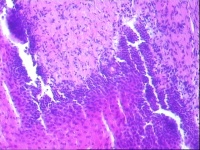

宫颈活检,请教老师

性别

女

年龄

62岁

临床诊断

一般病史

宫颈液基ASC-US。

标本名称

宫颈组织

大体所见

灰白色米粒大组织5块。